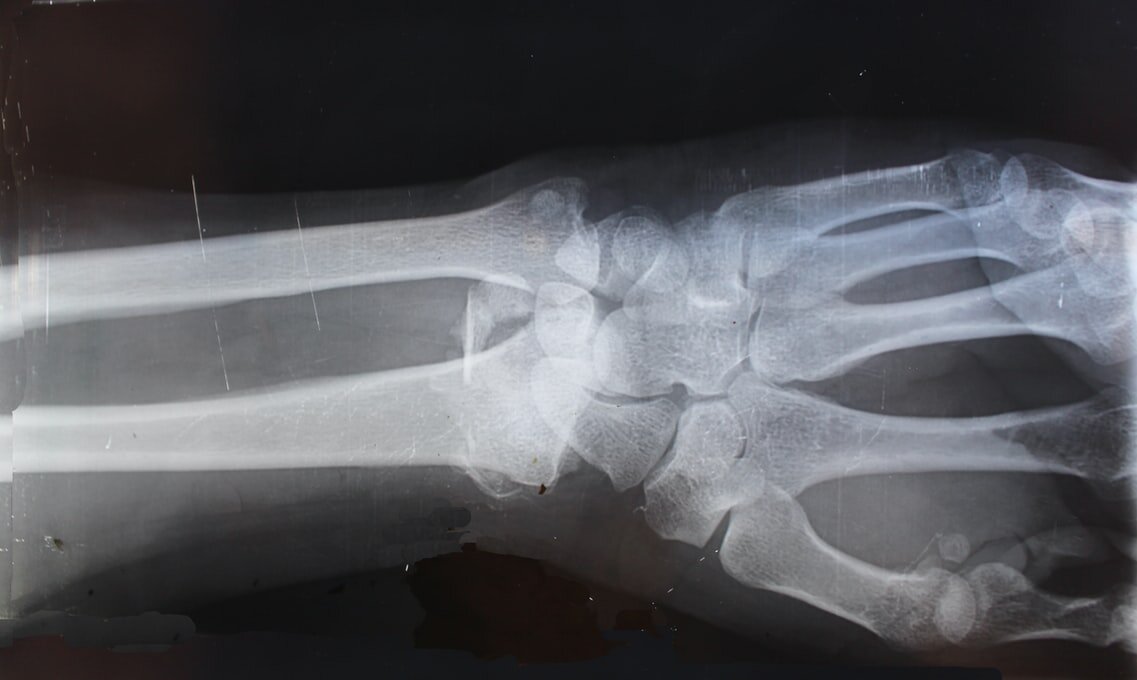

Однако в ортопедической практике, к сожалению, врачи чаще всего сталкиваются с пациентами, которые уже получили переломы после незначительного воздействия. Наиболее частые из них — переломы тел позвонков или таза в результате падения на ягодицы со стула, кровати. Также нередки переломы нижней трети лучевой кости, шейки плеча, шейки бедренной кости. Александру запомнилась пациентка, которая получила перелом тел семи позвонков, когда передвигала с мужем холодильник.

В диагностический минимум входят рентгенологические методы исследования, которые позволяют измерить костную плотность (рентгеновская компьютерная томография, остеоденситометрия). Если плотность снижена, выясняют причину возникновения остеопороза. Для этого нужно биохимическое исследование крови с определением уровней кальция, фосфора, витамина D, гормонов щитовидной и паращитовидных желез, анализом маркеров резорбции (разрушения) костной ткани. В некоторых случаях назначают УЗИ желез внутренней секреции.